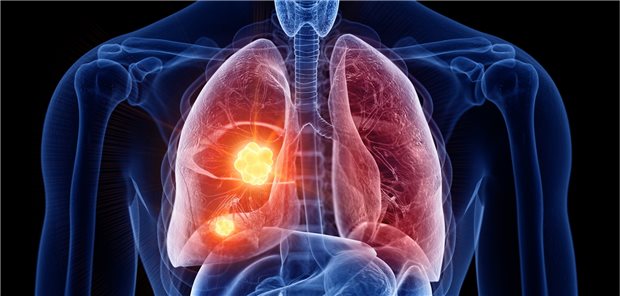

Wenn das avisierte Lungenkrebsscreening das kann, was es bewirken soll, werden künftig vermehrt Frühstadien gefunden. Die Dignität eines Herdes ist zu klären, die Methoden dazu sind noch unzureichend.

Patienten mit bestimmten Formen eines Lungenkarzinoms oder Basalzellkarzinoms profitieren von einer Therapie mit Cemiplimab. Das haben die Studien EMPOWER-Lung 1 und EMPOWER-BCC 1 ergeben.